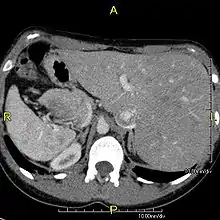

Axial CT image showing situs inversus (liver and IVC on the left, spleen and aorta on the right) in a patient with Kartagener syndrome.

The condition affects all major structures within the thorax and abdomen. Generally, the organs are simply transposed through the sagittal plane. The heart is located on the right side of the thorax, the stomach and spleen on the right side of the abdomen and the liver and gall bladder on the left side. The heart's normal right atrium occurs on the left, and the left atrium is on the right. The lung anatomy is reversed and the left lung has three lobes while the right lung has two lobes. The intestines and other internal structures are also reversed from the normal, and the blood vessels, nerves, and lymphatics are also transposed.

If the heart is swapped to the right side of the thorax, it is known as "situs inversus with dextrocardia" or "situs inversus totalis". If the heart remains on the normal left side of the thorax, a much rarer condition (1 in 2,000,000 of the general population), it is known as "situs inversus with levocardia" or "situs inversus incompletus".